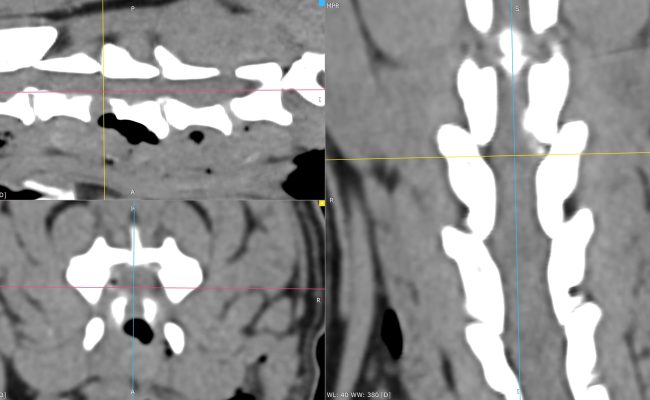

Exérèse d’une tumeur méningée thoracique chez un chat.

L’image de gauche correspond aux reconstructions scanner multiplanaires mettant en évidence une tumeur méningée thoracique responsable d’une compression médullaire sévère. Les flèches soulignent la prise de contraste intense et bien délimitée de la masse, ainsi que son effet compressif marqué sur la moelle épinière. L’aspect est typique d’une lésion extra-médullaire, clairement distincte d’une hernie discale, expliquant le tableau neurologique initial très grave avec paralysie complète de stade V.

L’image centrale illustre l’abord chirurgical peropératoire après exposition de la vertèbre concernée. Une laminectomie ciblée est réalisée afin d’accéder à l’espace épidural et à la lésion. Cette étape requiert une dissection extrêmement minutieuse, dans un environnement anatomique restreint, afin de préserver l’intégrité de la moelle épinière et des structures adjacentes.

L’image de droite montre l’aspect de la tumeur après ouverture osseuse et exérèse. La masse est individualisée puis retirée avec précision, permettant une décompression complète de la moelle épinière. Malgré la sévérité du déficit neurologique préopératoire, l’évolution clinique a été très favorable, avec une récupération fonctionnelle complète du chat après l’intervention, illustrant l’intérêt et l’efficacité de ce type de chirurgie neuro-oncologique lorsqu’elle est réalisée dans des conditions optimales.